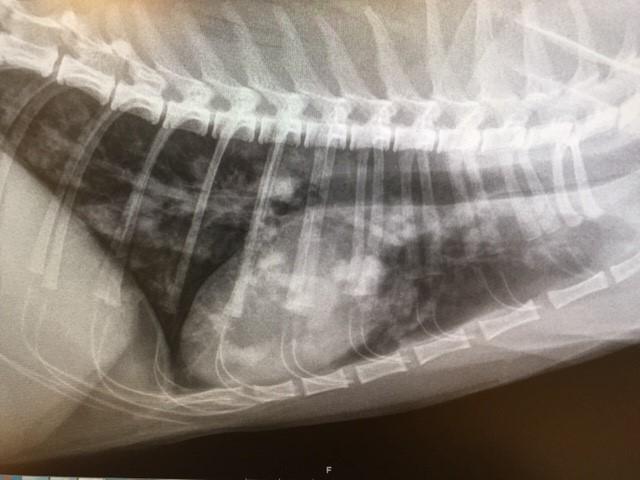

Ofte vil dyrlægen ligeledes tage blodprøver fra katten eller foretage en røntgenundersøgelse af dens lunger.